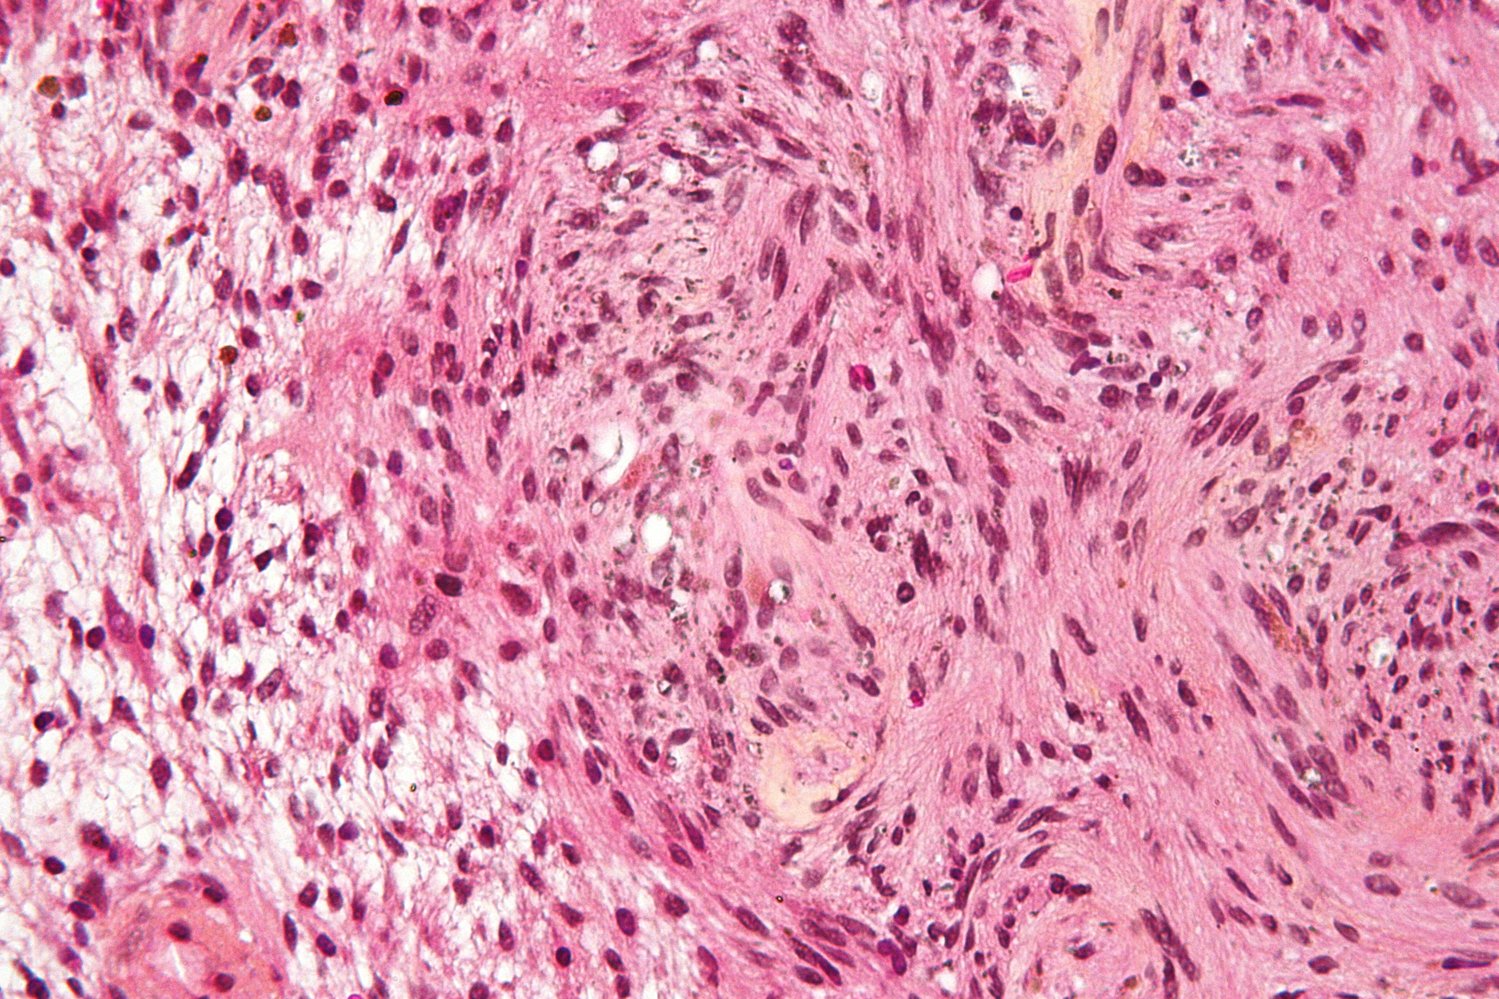

• Microscopic findings

• Spindle cells in palisades (Antoni A tissue) alternating with myxoid hypocellular areas (Antoni B tissue)

• S-100 positive